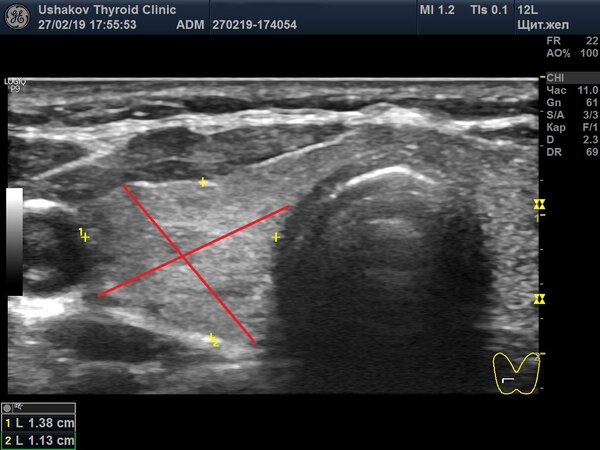

1. Правильность замеров. Измерения в поперечной проекции должны проводиться строго по ширине и глубине, а не крест-накрест (в виде буквы «Х»), что является ошибкой.

Красные линии на изображении демонстрируют ошибочный способ измерения.